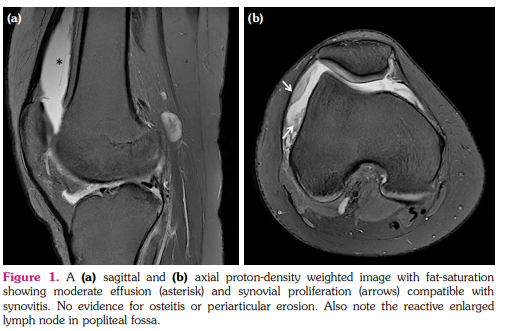

An 18-year-old woman with a history of allergic rhinitis and atopic dermatitis, presented for her pruritic lesions. The pruritic nodules started from the lumbar area nine years ago and subsequently spread to entire body. Topical corticosteroids, oral antihistamines, systemic corticosteroids, and methotrexate were prescribed with no long-term benefits. Dermatological examination revealed hyperkeratotic plaques involving the trunk and extremities. Histopathological evaluation of the lesions was compatible with the diagnosis of prurigo nodularis. She was started on oral cyclosporine 200 mg for seven months; however, within the last month of cyclosporine treatment, her complaints increased, leading us to switch to dupilumab. Although her clinical manifestations and pruritus improved, she developed mild right knee swelling, warmness, and arthralgia after the first maintenance dose following the loading dose. Upon questioning, we recognized that the patient developed reactive arthritis in the right knee, when she was 10 years old. Until now, she stayed asymptomatic. She was consulted to rheumatology department and effusion was detected by right knee ultrasonography and arthrocentesis was performed which revealed no bacterial growth. Elevated C-reactive protein and erythrocyte sedimentation levels were noted. Rheumatological markers were all negative. Right knee magnetic resonance imaging showed moderate effusion along with synovial proliferation consistent with synovitis; no periarticular erosion, osteitis or ligamentous anomaly were detected (Figure 1). She was diagnosed with dupilumab-induced exacerbation of inflammatory arthritis and was started on oral diclofenac and intraarticular steroid injection which resulted in symptomatic relief. Therefore, dupilumab treatment was continued.